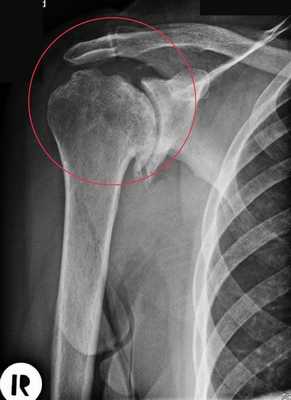

Артроз плечевого сустава на рентгене.

При травме достаточно рентгеновского снимка, чтобы понять, насколько серьезно повреждение и какие меры необходимо принимать. Но иногда точно понять причину болей и нарушения подвижности по снимкам не представляется возможным, и не всегда проблема кроется в патологических процессах непосредственно в суставе.

Например, такое опухолевое образование как энходрома (доброкачественная опухоль из хрящевой ткани), может подобраться к нему, развиваясь в плечевой кости. Если причиной боли является сильно разросшаяся энходрома - операция плечевого сустава неизбежна.